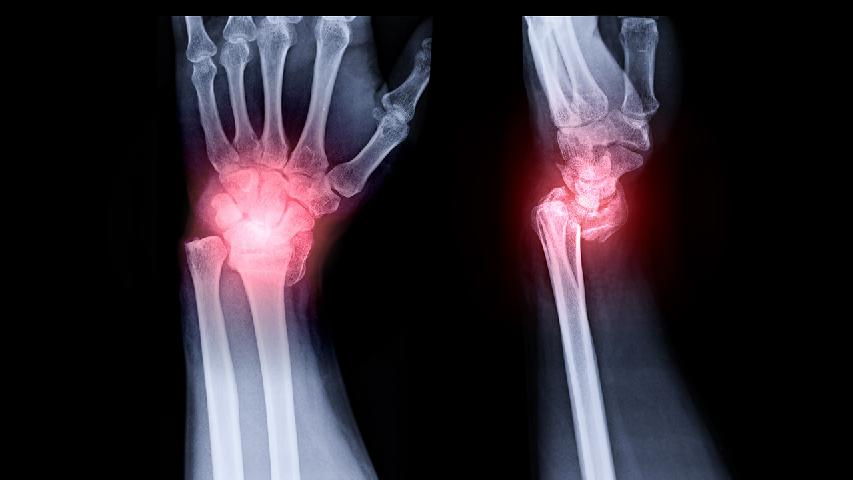

O型腿矫正手术方式主要有截骨矫形术、外固定架矫形术、骨骨骺阻滞术、Ilizarov技术等。手术选择需根据年龄、骨...

O型腿可以通过整形手术矫正,主要方法有截骨矫形术、外固定架矫形术、生长引导术、微创矫形术等。 1、截骨矫形术 适...